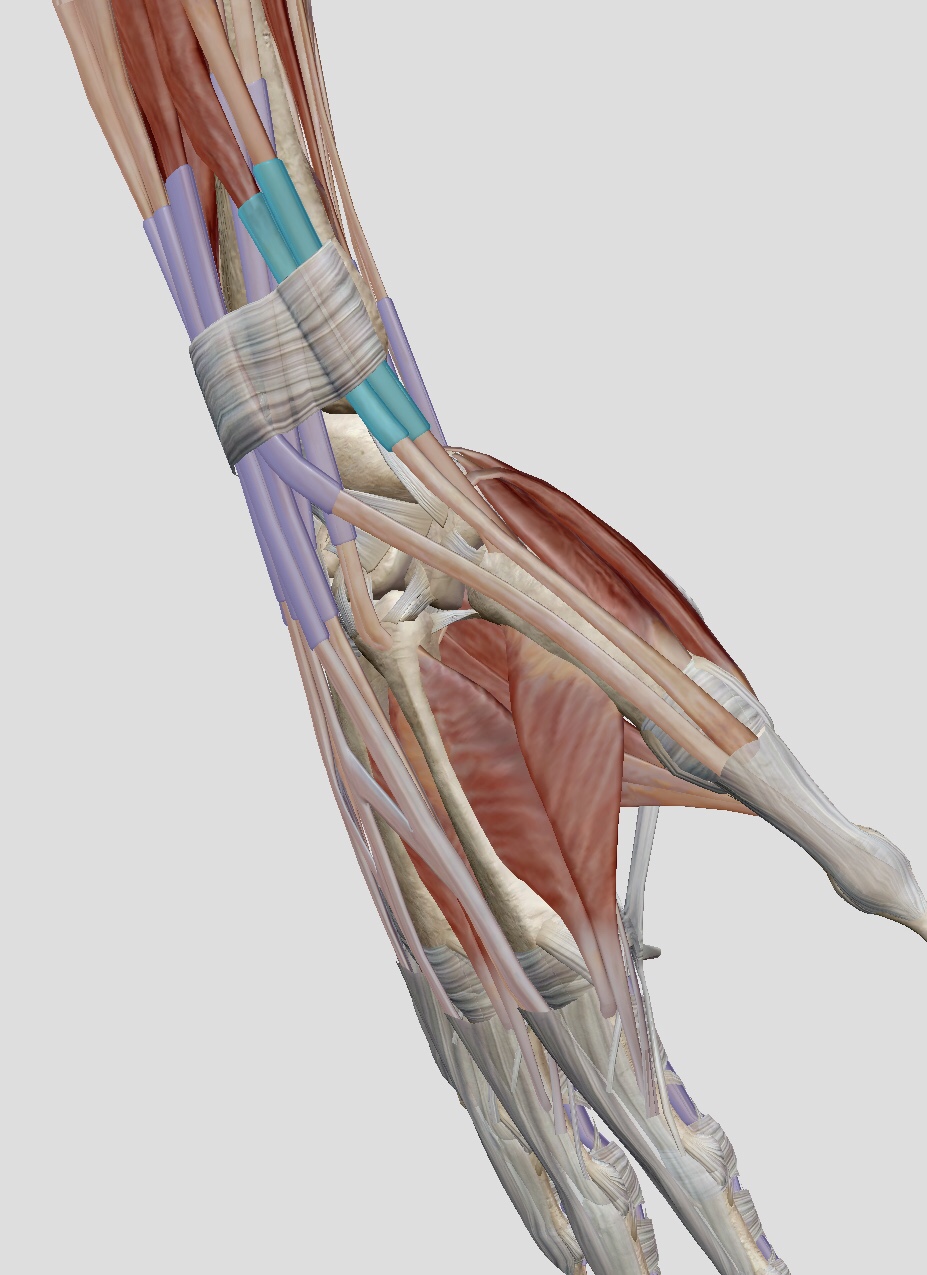

「腱鞘」は全ての腱にあるわけでは無いんです。

まず、手首はおなじみなんですけど、よく言われる腱鞘炎は「長母指外転筋腱鞘」と「短母指伸筋腱鞘」の炎症です。(分かりずらいかもしれませんが、水色の部分です)

この腱鞘がなんで炎症を起こすかは、使いすぎによるものなんですけど、使い過ぎでどうして炎症を起こすかは、それぞれに見解が違うんだと思います。